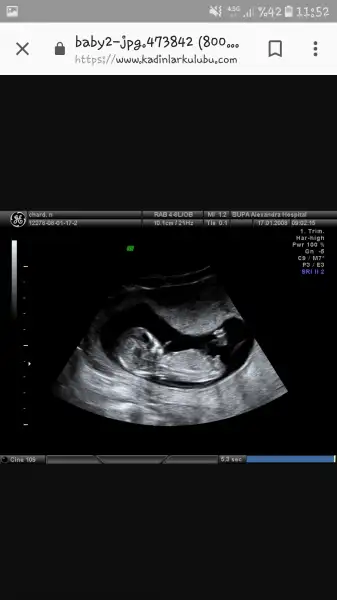

Ayy maşallah ne kadarda net ozele mi gidiyorsun cnmEki Görüntüle 2160356 11+6'dan herkese selamlarr. :) Doktora çarşamba gitmiştik. İkili test için 45 mm olması lazımmış. 3 gün önce 43 küsürdü. Şimdi 51 mm olmuş. :) İkili test için kan verdim, 1 hafta sonra çıkıyormuş. Bebeğimin hareketlerini de ilk kez gördük. Çokkkkk güzeldi. :))))) Ayaklarının birini havaya kaldırıyor diğerini indiriyordu. :))))))